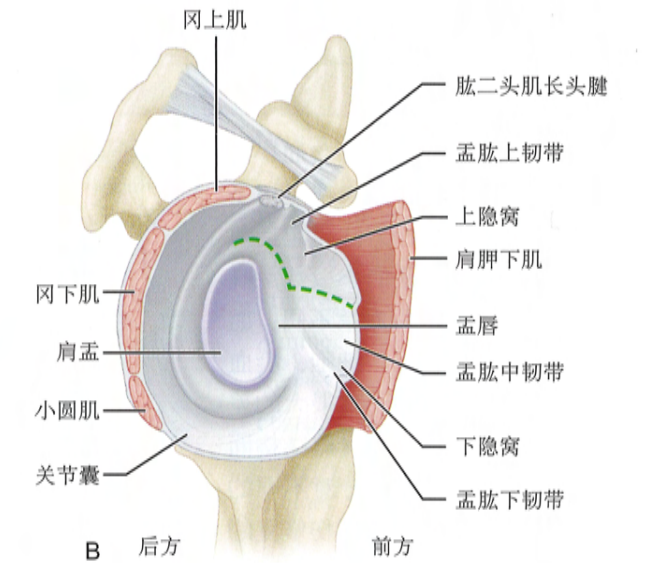

解剖